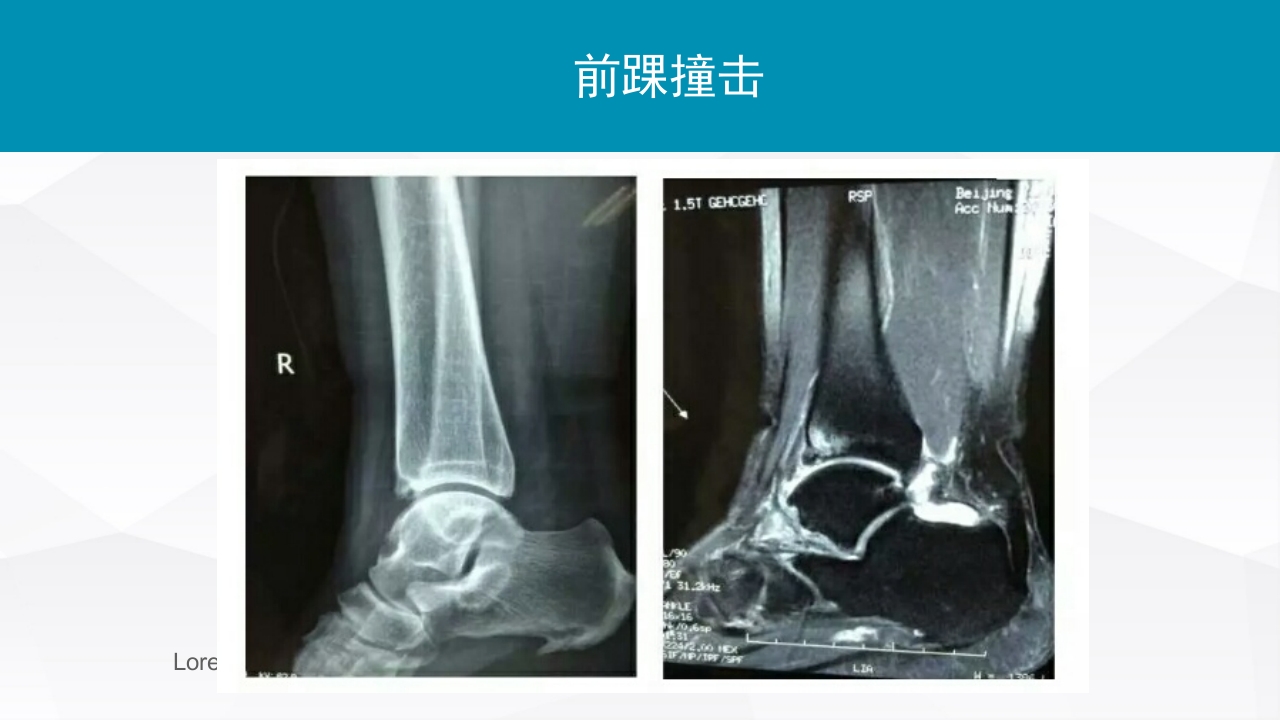

踝关节扭伤评估和治疗 LOREM IPSUM DOLOR 目CONTENTS 录 01 踝关节扭伤及损伤评估 02 踝关节扭伤的保守治疗 03 踝关节扭伤的手术治疗 踝关节扭伤 踝关节扭伤是最常见的运动损伤 85%为外踝损伤 踝关节扭伤发生机制 小腿外旋合并后足旋后 接触地面瞬间,踝关节跖 屈及内翻容易导致外踝扭伤 踝关节扭伤 踝关节外侧韧带损伤的发生率 距腓前韧带(ATFL)几乎总会损伤 跟腓韧带(CFL)受伤发生与50%~75%踝关节扭 伤 距腓后韧带(PTFL)损伤率低于10% 踝关节扭伤不能得到正确治疗 50%出现慢性踝关节不稳 15%进展为踝关节骨性关节炎 踝关节急性损伤的评估 损伤分度 I 损伤程度 ATFL损伤 II ATFL撕裂 III ATFL断裂 CFL断裂 查体发现 轻度肿胀,关节 不稳 治疗 负重功能锻...